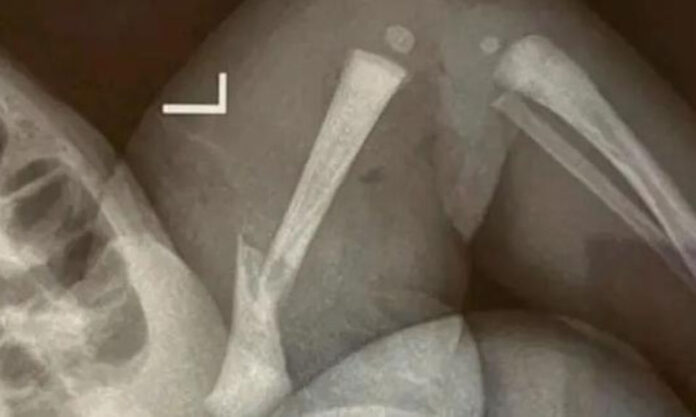

当地中文新闻 泰州医院医疗事故导致新生儿腿部骨折 14th May 2024 Latest News Tasty Solutions on the Menu at Shanghai Climate Week Why is the Shanghai Government Sniffing around Our Back Yard? Nanjing’s International Flights; All Change for Summer Schedule Gorillas! Who wants to Go See Nanjing Zoo’s Newly Arrived Primates?! Image courtesy The Paper 婴儿出生后,泰州靖江市人民医院的工作人员无视婴儿不断的哭闹。 医院承认技能问题是原因,但无法回应家长的要求,即对孩子随后的腿部问题负责。全文详见此链接;点此链接(英文)阅读有关泰州的最新报道。 Visiting Nanjing Wuxi Extends Air Links with Hong Kong and Macau 南通公交车事故; 阿姨发声,倾诉全中国的悲痛 Tourism Authority of Thailand Roadshow Drives Demand in Nanjing 61名团伙成员因在TikTok上销售假课程而在连云港被捕 Master Chinese Linguist Unaware of Deeds Until Death; Zhu Dexi